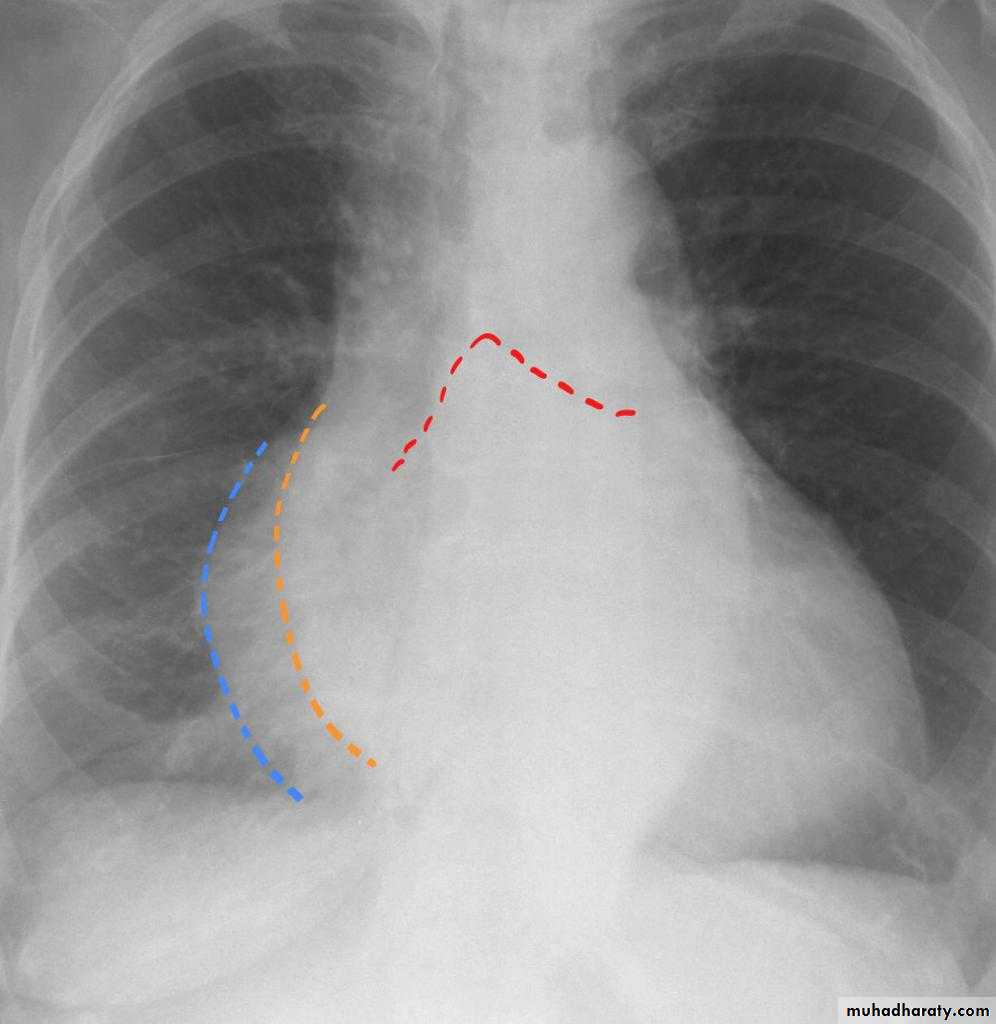

Cardiothoracic ratio (CTR) = Cardiac Width : Thoracic Width

A CTR of greater than 1:2 (50%) is considered abnormal. This however, assumes the projection is Posterior-Anterior (PA), and that cardiac size is not exaggerated by factors such as patient rotation or an incomplete breath in .

The cardiothoracic ratio aids in the detection of cardiomegaly, or more broadly, enlargement of the cardiac silhouette. .

Enlargement of the cardiac silhouette on chest x-ray can be due to a number of causes :

1.cardiomegaly (most common cause by far)2.pericardial effusion

3.anterior mediastinal mass

4.prominent epicardial fat pad

Causes of cardiomegalyThere are many aetiologies for cardiomegaly. The list includes:

*Mitral valve disease*Congestive heart failure

*Congenital heart disease